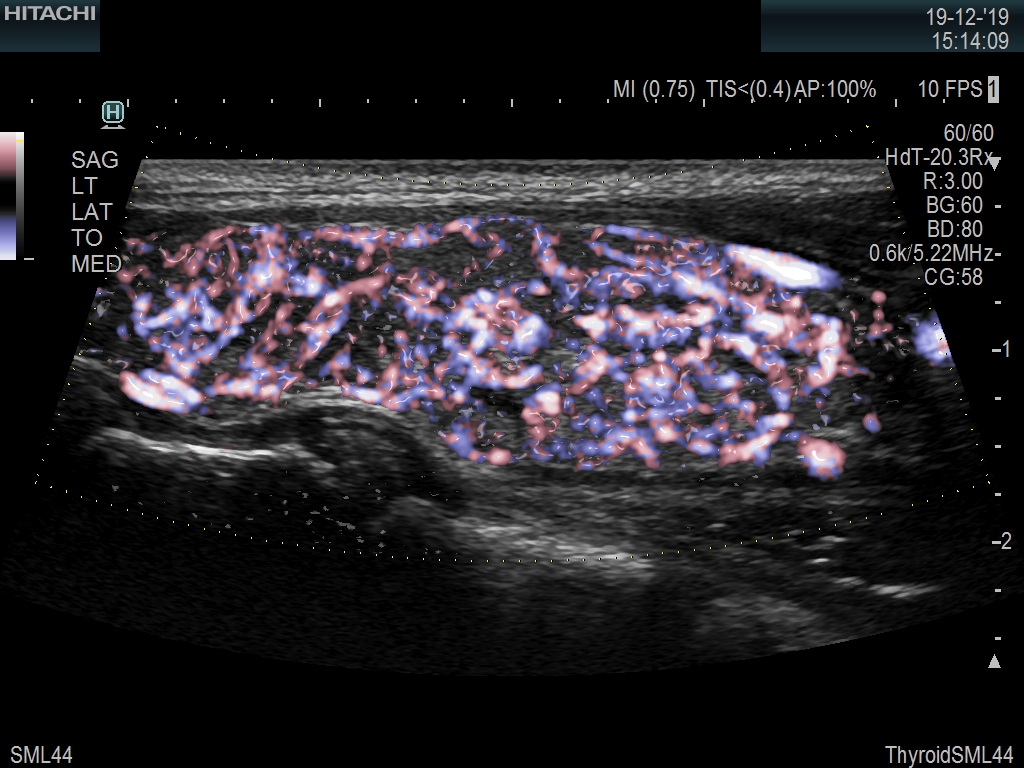

Superior guidance for all applications

Fujifilm Healthcare Americas is committed to designing tools that help surgeons navigate inside the human body and provide the necessary information to immediately make critical surgical decisions.

Fujifilm Healthcare's dedication to Surgeons provides outstanding ultrasound technology, professional support and the specialized tools necessary to best perform comprehensive real-time ultrasound imaging in Breast Surgery, General Surgery, Laparoscopic Surgery, Neurosurgery, Robotic Surgery and Surgical Oncology.

The Fujifilm Healthcare transducer utilizes the full benefits of the Wrist Articulation™ of the robotic instruments to capture real-time ultrasound imaging even at complex angles and difficult-to-reach areas.

A critical function of robotic ultrasound guidance is tumor margin identification. Fujifilm's family of robotic probes all have the optimum location of the attaching mechanism that allows for full wrist articulation of the probe. The result is an increased confidence that the tumor margins have been completely identified.

Imaging Clearly Defined

State-of-the-art digital architecture and advanced imaging features to redefine the capabilities of surgical ultrasound.